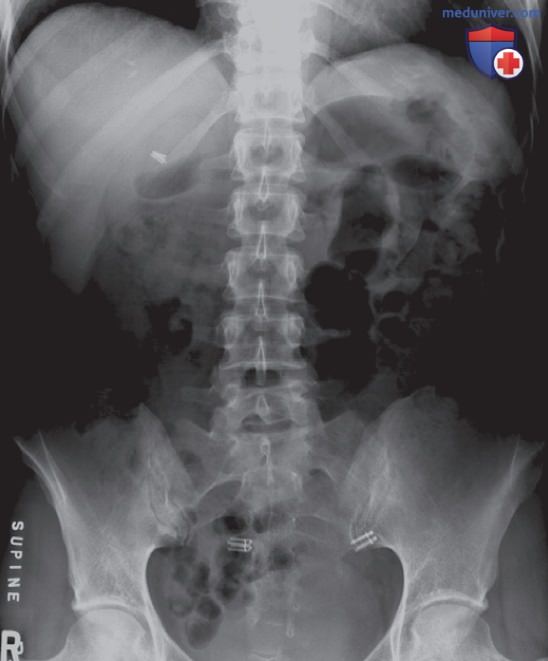

Рисунок 1. Рентгенограмма органов брюшной полости, полученная при использовании центральной ионизационной камеры вместо периферических камер. Если камера располагается под поясничным отделом позвоночника, то накопителю требуется больше времени для достижения максимального уровня, позволяющего завершить экспозицию. Это вызвано большим количеством атомов в кости по сравнению с мягкими тканями, а значит и большим поглощением фотонов. Таким образом, рентгенограмма будет переэкспонирована, что может привести к сатурации мягких тканей.

- Избыточная экспозиция возникнет при выборе камеры под структурой, характеризующейся большим количеством атомов, большей толщиной или плотностью, чем область ЗИ (рис. 1)